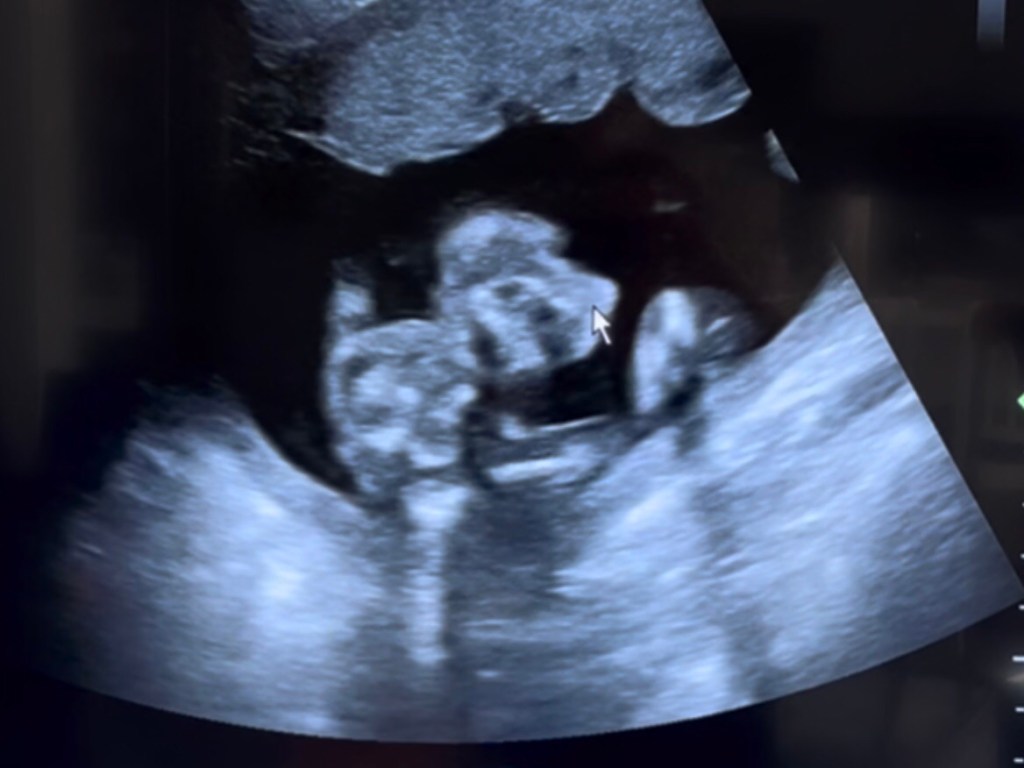

The anatomy scan was yesterday, and the technician, who has been doing this for almost a decade, said everything made her happy. (You know, the legal way to say everything looks good, but without giving any official diagnosis, since she’s the technician, not the radiologist.) All the measurements were coming up as perfectly where the kid would be expected to me at this point, which was cool to hear. The whole spine was there and beautifully in line and full. It was such a relief to see that specifically. Hands and feet and arms and ears and nose and eyes and eye lenses and lips are all there and proper, properly developed. They all are fully developed, and just will continue growing. Super exciting news.

And we still don’t know the gender. Determined we don’t want to mess with anyone else’s reactions about it, nor do I want to risk any depression for myself at a disappointment, so we stuck with finding out when the baby arrives in January. I’ll be flooded with hormones and chemicals to help me love and adore and care for this baby no matter the gender, so it’s the best time to find out the gender, one way or the other.

P.S. Now, if anyone asks what we’re having, I can say honestly that is looks like a cartoon T-Rex.

Well, we had a success today. Two, in fact. I made it to an early Mass at Church, and on my own. I didn’t make it for the whole time still, but I made it all on my own. Then, the ultrasound for the anatomy scan went really well. All things were present and measured appropriate sizes for the exact current length of time the baby has been growing inside of me. The technician couldn’t give officially a result, but was legally allowed to say that she was happy with everything she saw and she answered a lot of questions along the way that eased much anxiety I had been carrying about whether the baby was developing properly and all. Turns out that it all measure up and lines up quite well. Also, still don’t know about gender, intentionally so, but it is now starting to stress me for real. Everything in me wants this one to be a healthy girl. It also was already feeling like a girl, with no clear explanation as to why it feels that way. The first one felt like a boy. This one feels like a girl. However, I am having doubts now, and it is stressing me. Ugh.